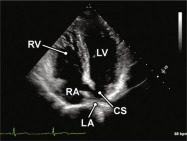

| 2.18. Mặt cắt 4 buồng từ mỏm nghiêng ghi hình xoang vành |

||||||||

|

|

Cửa sổ siêu âm từ mỏm tim

Mặt cắt 4 buồng Từ mặt cắt 4 buồng từ mỏm, nghiêng chùm siêu âm ra sau để ghi hình xoang vành. |

Xoang vành (CS) Nhĩ phải (RA) Thất phải (RV) Thất trái (LV) Nhĩ trái (LA) |

|||||